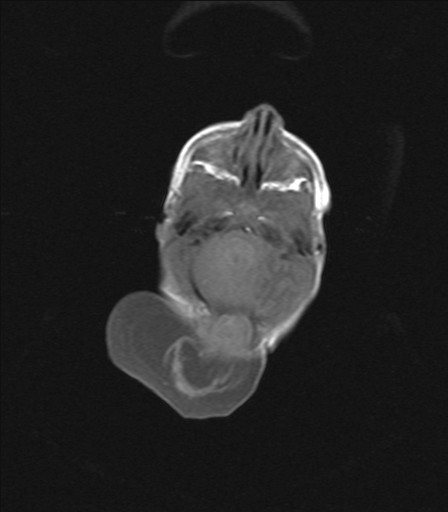

Epidermoid

Epidermoid is a cell rest in the nervous tissue which forms a cyst filled with keratin. It can occur in the brain or spinal cord. MRI gives accurate preoperative diagnosis. Surgery is safe and curative.